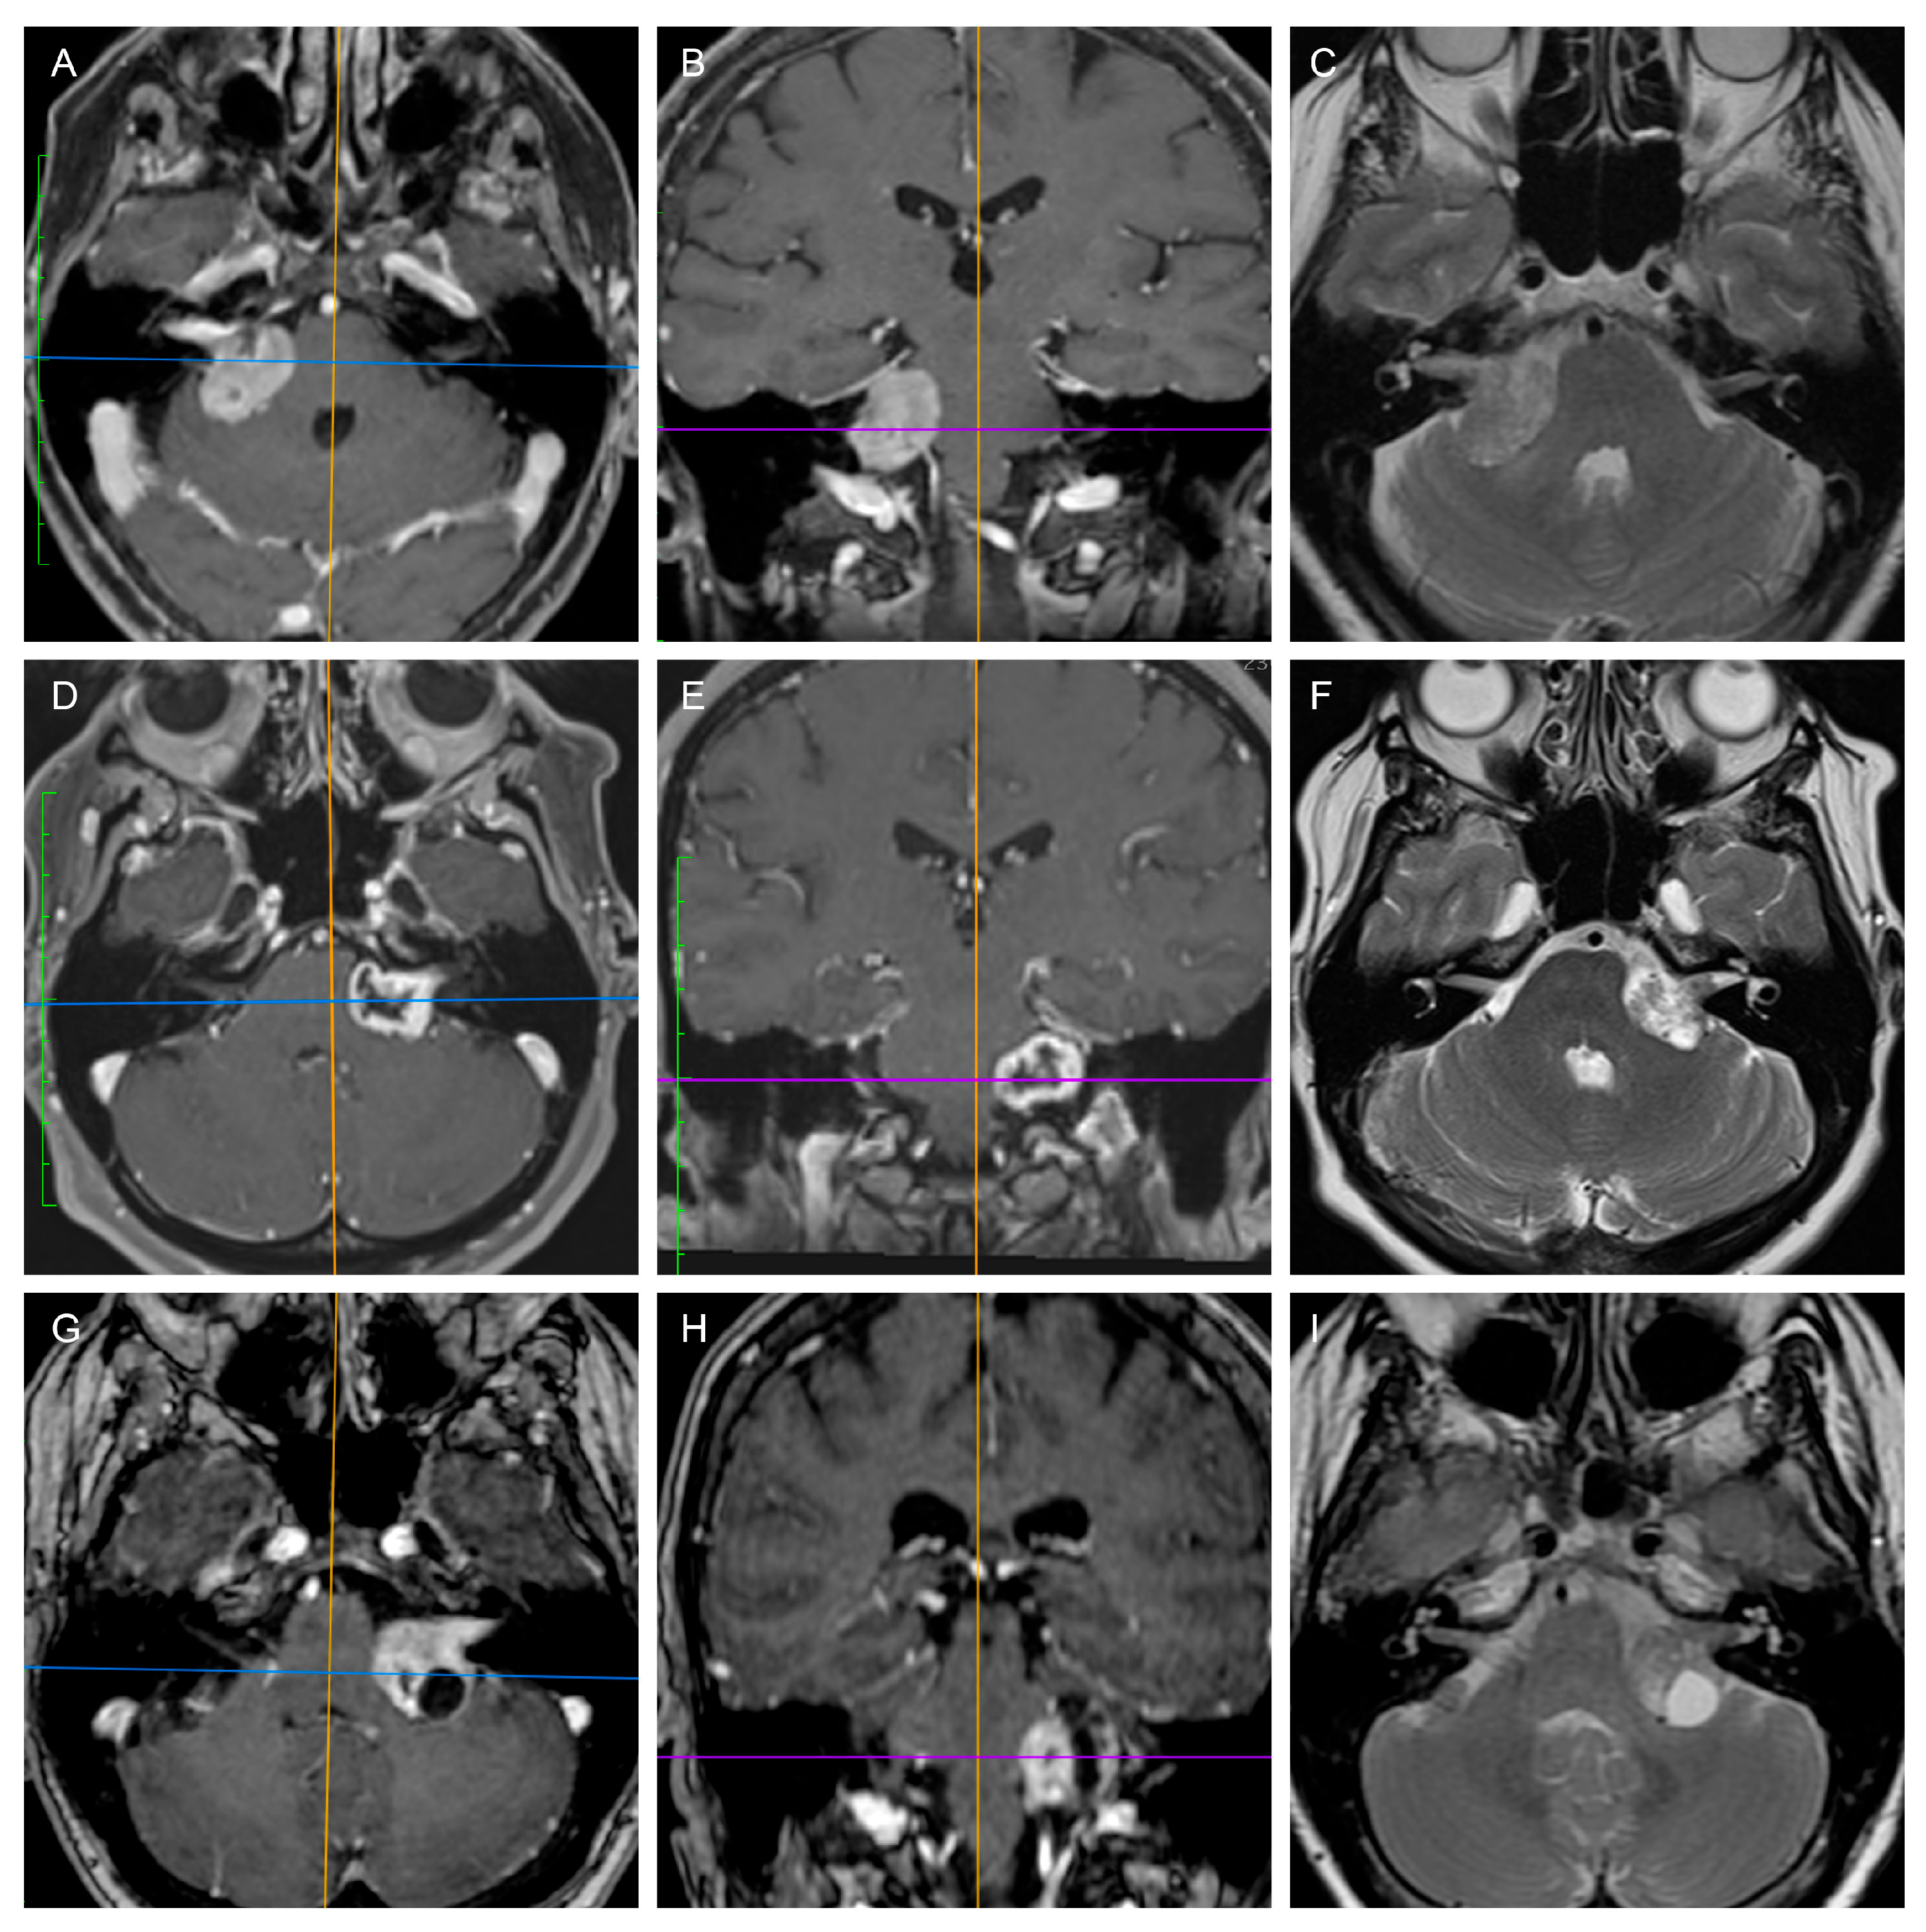

2. Materials and Methods

3. Results

3.1. Predicting the Consistency